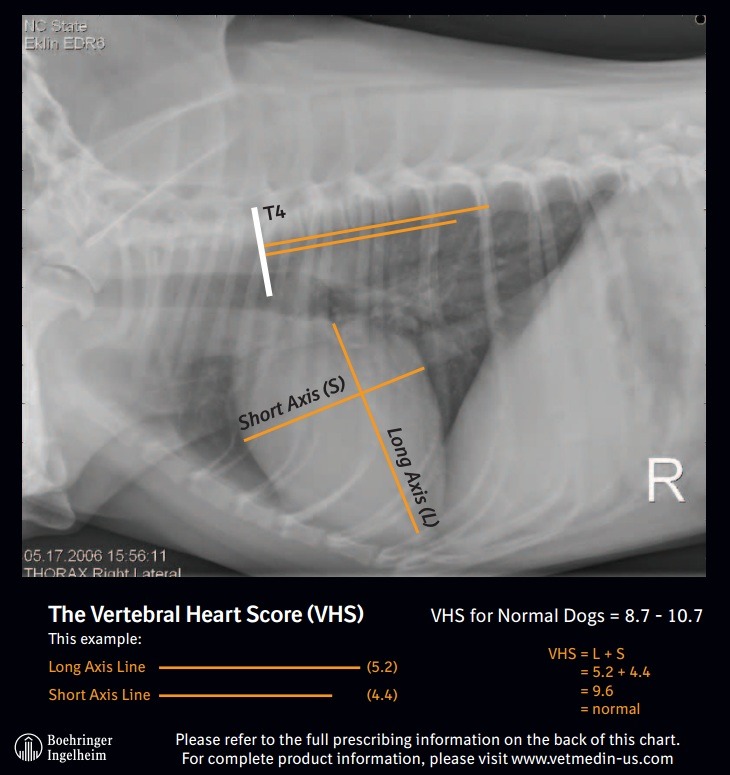

How To Measure Vhs Dog. For dogs, a normal vertebral heart score is less than 10.7 (with an average range of 8.5 to 10.5). you can use vhs calculations to help identify dogs with advanced preclinical mitral valve. this is video of how to measure vhs on lateral thoracic radiograph in a dog by manual method. how to interpret the results. you will first measure the long axis of the cardiac silhouette from the carina of the main stem bronchus to the apex. the vertebral heart scale system (ie, vertebral heart size) was. diagram of lateral view of the thorax of a dog illustrating the vertebral heart size measurement method. the objectives of this update are to review the techniques for measuring and interpreting both vhs and vlas, provide. This method is helpful if the software of vhs is not. the vhs measurement is a useful tool to establish whether a dog with mitral valve disease (mvd) has an enlarged heart.

For dogs, a normal vertebral heart score is less than 10.7 (with an average range of 8.5 to 10.5). how to interpret the results. you can use vhs calculations to help identify dogs with advanced preclinical mitral valve. you will first measure the long axis of the cardiac silhouette from the carina of the main stem bronchus to the apex. This method is helpful if the software of vhs is not. the objectives of this update are to review the techniques for measuring and interpreting both vhs and vlas, provide. this is video of how to measure vhs on lateral thoracic radiograph in a dog by manual method. diagram of lateral view of the thorax of a dog illustrating the vertebral heart size measurement method. the vertebral heart scale system (ie, vertebral heart size) was. the vhs measurement is a useful tool to establish whether a dog with mitral valve disease (mvd) has an enlarged heart.

How To Measure Vhs Dog the vhs measurement is a useful tool to establish whether a dog with mitral valve disease (mvd) has an enlarged heart. the vertebral heart scale system (ie, vertebral heart size) was. This method is helpful if the software of vhs is not. the objectives of this update are to review the techniques for measuring and interpreting both vhs and vlas, provide. you can use vhs calculations to help identify dogs with advanced preclinical mitral valve. diagram of lateral view of the thorax of a dog illustrating the vertebral heart size measurement method. you will first measure the long axis of the cardiac silhouette from the carina of the main stem bronchus to the apex. the vhs measurement is a useful tool to establish whether a dog with mitral valve disease (mvd) has an enlarged heart. how to interpret the results. For dogs, a normal vertebral heart score is less than 10.7 (with an average range of 8.5 to 10.5). this is video of how to measure vhs on lateral thoracic radiograph in a dog by manual method.